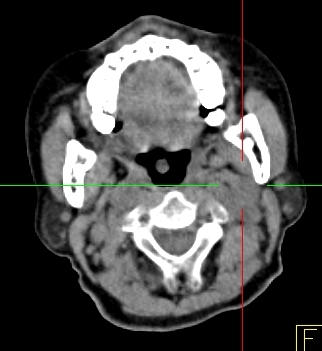

Hình 2 ghi lại kết quả chụp PET/CT của bệnh nhân Trịnh Th. T. L., nữ, 66 tuổi, gần đây thấy xuất hiện ù tai trái, hạch cổ trái. Sinh thiết hạch cổ trái là ung thư biểu mô di căn hạch chưa rõ nguyên phát. Bệnh nhân được chỉ định chụp PET/CT để tìm ổ ung thư nguyên phát.

Hình 2: Hình PET toàn thân và hình PET/CT thấy tổn thương ở vùng vòm (mũi tên đỏ) và hạch góc hàm (mũi tên xanh) tăng hấp thu FDG. Hình ảnh hướng đến ung thư vòm di căn hạch góc hàm trái. Bệnh nhân đi nội soi và bấm sinh thiết vùng vòm trái cho kết quả ung thư biểu mô tế bào vẩy.